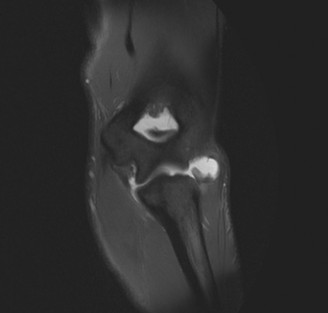

The correct answer is (B). An MRI showing a rotator cuff tear is considered diagnostic of a rotator cuff tear because of its high sensitivity, specificity, and accuracy. It has superb soft tissue imaging abilities (see Fig. 2–5). However, it should be noted that while MRI usually can differentiate between partial- and full-thickness rotator cuff tears, this varies with the power and accuracy of the MRI facility. This is also true with the ability of MRI to differentiate between partial-thickness rotator cuff tears and subacromial bursitis. An arthroscopy is needed for definitive differentiation of these pathologies.

Figure 2–5_Coronal oblique view MRI slice of a left shoulder. (Reproduced with permission from Smithius R and van de Woude HJ. Shoulder MR Anatomy: Normal Anatomy, Variants, and Checklist. _Radiology Assistant. April 2, 2012.)

Figure 2–8_Reproduced with permission from Stadnick ME. _Partial Rotator Cuff Tears. MRI Web Clinic. 2007 (Apr).

The correct answer is (A). These are best diagnosed on an MRI as seen in the imaging provided; addition of intra-articular contrast can further improve this study. Answer B, full-thickness rotator cuff tear, is incorrect as the bursal side of the tendon can be seen to be in continuity. Answer C, a SLAP lesion, will be visualized as a labral tear on a coronal MRI and will be found at the biceps root. Answer D, an ALPSA lesion, will be most clearly seen on an axial MRI. It is a variant of a Bankart lesion where the labrum is displaced medially and inferiorly rolling down the glenoid neck underneath the periosteum.

MRI remains the most popular imaging modality for diagnosing rotator cuff tears. Normal rotator cuff tendon appears dark on both T1 and T2 sequences. Tears may be noted as being full-thickness, articular-sided, bursal-sided, or intrasubstance. They are visualized as a disruption in the regular contour of the tendon and increased signal intensity on T2 sequences. Occasionally, an MR arthrogram may provide additional information regarding a cuff tear, although this is not routinely ordered.

What MRI sequence and plane is best for viewing supraspinatus rotator cuff tears?

The correct answer is (D). T2 sequence causes most soft tissues, including muscle and tendon, to appear dark and inflammation, such as at the site of a tear, to appear bright. This means that if there is a rotator cuff tear, there will be a bright spot along the course of the dark rotator cuff tendon. This is easiest to pick out in the coronal plane because the tendon runs in this plane, allowing one to view the entire supraspinatus tendon and tear in one cut.